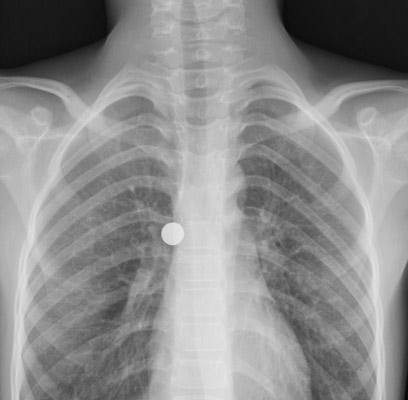

הורי הילד, זוג ממרכז הארץ, הגיעו ביום ראשון בשעות הערב לחדר המיון יחד עם בנם. ההורים סיפרו כי בנם החזיק בפיו סוללה, וככל הנראה הוא השתעל או השתנק והסוללה נבלעה. בבית החולים ביצעו צילום רנטגן שאושש את ההשערה.

"בצילום ראינו את הסוללה בתוך הגוף ונראה היה שזה בריאות", סיפר ד"ר יורם שטרן, מנהל השירות למחלות דרכי

הנשימה וקול ביחידת אף אוזן גרון במרכז שניידר. "זה יחסית נדיר, כי לרוב במקרים דומים מדובר בבליעה של הסוללה ולא בשאיפה. סוללות מכילות חומצות, שמאכלות והורסות רקמות. היתה דחיפות להוציא את הסוללה בהקדם, כדי שלא ייגרם נזק לרקמת הריאות". ד"ר שטרן הוסיף כי אם הסוללה היתה מתפרקת, עלול היה להיגרם נזק בריאותי ממשי לילד.

צילום הרנטגן של הילד במיון

באדיבות ביה"ח שניידר